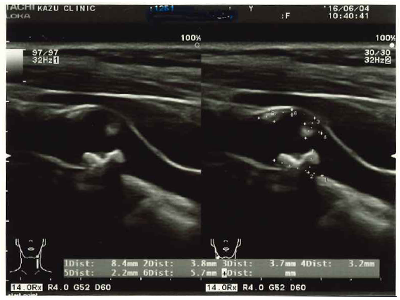

高血圧による血管壁にかかる圧力、また血液中のコレステロールや中性脂肪の上昇で血管を損傷して内皮内側にプラークができ、それが大きくなると動脈硬化となり、血管を閉塞して心筋梗塞や脳梗塞、大動脈に大きな動脈硬化が出来ると大動脈瘤の原因となります。体内の血管の動脈硬化の早期発見には頸動脈エコー検査が無痛で有効です。

頸部エコーやご自身の中性脂肪・コレステロール・レムナントなど調べて血管を若返らせましょう。